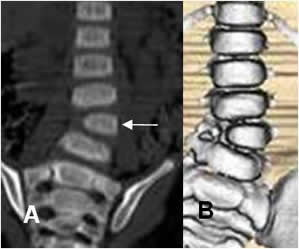

Fig 23. Hemivértebra.

A: TAC reconstrucción coronal y B: TAC reconstrucción en 3D. Hemivértebra en L4, con mínima desviación izquierda.